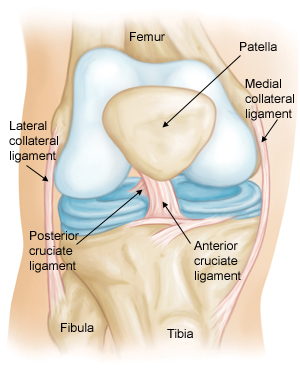

AnatomyThe bone structure of the knee joint is formed by the femur, the tibia, and the patella. The ACL is one of the four main ligaments within the knee that connect the femur to the tibia.

The knee is essentially a hinged joint that is held together by the medial collateral (MCL), lateral collateral (LCL), anterior cruciate (ACL) and posterior cruciate (PCL) ligaments. The ACL runs diagonally in the middle of the knee, preventing the tibia from sliding out in front of the femur, as well as providing rotational stability to the knee.

The weight-bearing surface of the knee is covered by a layer of articular cartilage. On either side of the joint, between the cartilage surfaces of the femur and tibia, are the medial meniscus and lateral meniscus. The menisci act as shock absorbers and work with the cartilage to reduce the stresses between the tibia and the femur.

Normal knee anatomy.